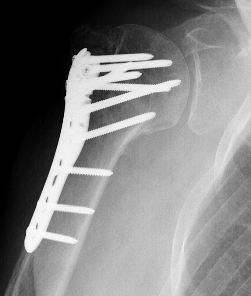

Apply plate

- lateral to biceps with single cortical screw in oblique hole

- check fluoroscopy - avoid having plate too high

- keep head out of varus to avoid cutout

- long inferomedial screws / kickstand screws

- locking screws

Plates

Synthes 3.5 mm LCP Proximal humeral plate surgical technique PDF

Long proximal humerus plates

Synthes 3.5 mm LCP Periarticular proximal humerus plate surgical technique PDF